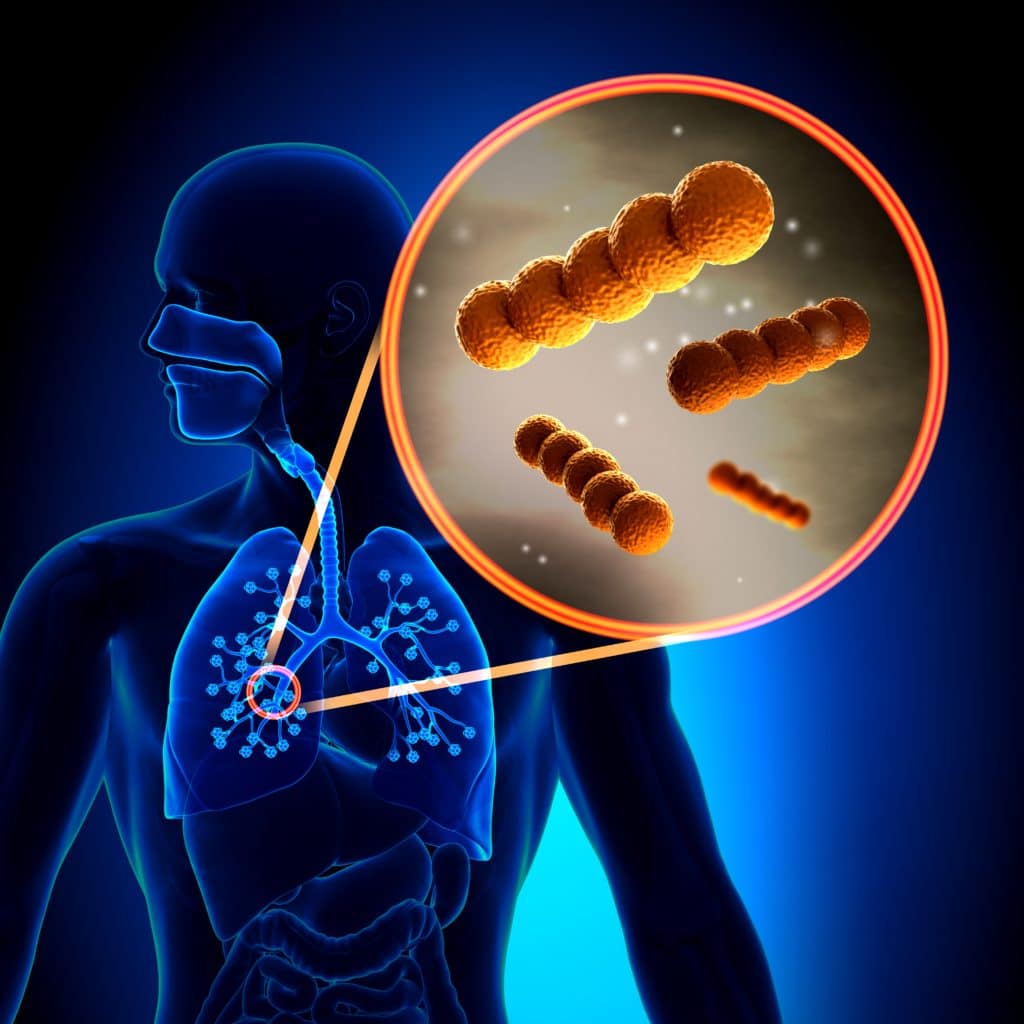

Фотографии бактерий, вызывающих бактериальные пневмонии у животных

Раздел: Другие животные